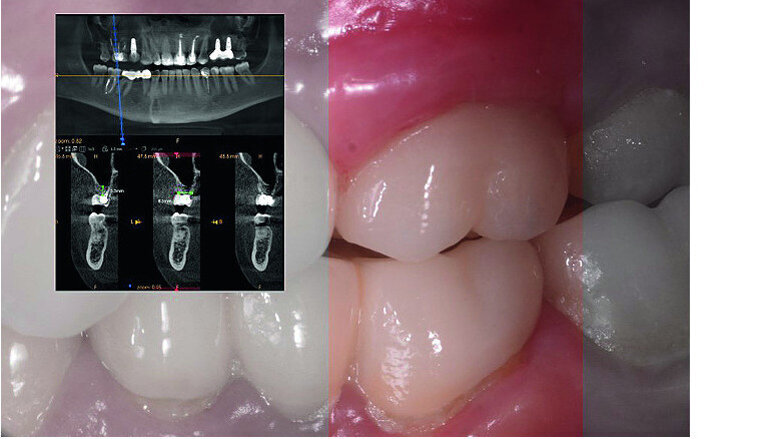

In March 2018, four months after the surgery, the prosthetic phase was started. An impression was taken with an intraoral scanner (CS 3600, Carestream Dental) using scan bodies for an impression at the implant head (MegaGen; Figs. 11a & b). The information was sent to the Anatomic Lab, where a crown was designed using a CAD programme. After the design of the crown had been finished, the information was sent to a milling machine (Amann Girrbach) and the crown was milled (Fig. 12). One week after the preparation, the definitive crown in monolithic zirconia was attached and the occlusion tested using T-Scan technology (Tekscan; Figs. 13a–c & 14).

Nowadays, we also have the possibility to superimpose the information related to the teeth and gingivae, received from the intraoral scan, over the bone-related information acquired with CBCT. It is therefore possible to plan the optimal positioning of implants with software to guide the surgery. Planning data is transferred to a surgical template that can be physically fabricated in various ways and with different materials. This guide will help the surgeon correctly position the implants without needing to raise a flap. [18]